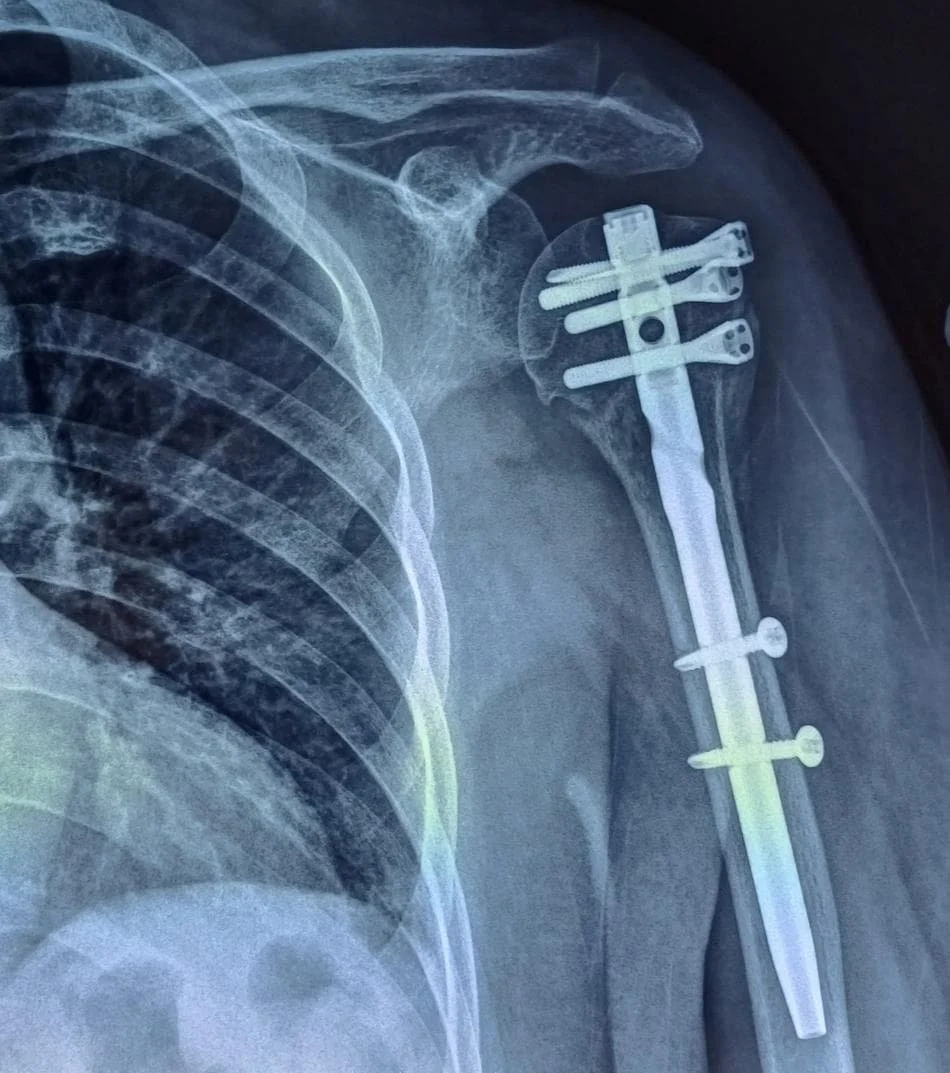

Surgical treatment for shoulder fractures is considered when the bones are displaced, unstable, involve the joint surface, or cannot heal properly with conservative care. The choice of surgery depends on which bone is fractured, the severity of displacement, the patient’s age, and functional needs.

Surgery involves realigning the bone fragments and using plates, screws, or other hardware to stabilise them.

xray of proximal humerus fracture fixation

1.⁠ ⁠Open Reduction and Internal Fixation (ORIF)

What it is: The surgeon repositions (reduces) the broken bone pieces and secures them with plates, screws, or pins.

Commonly used for: Displaced clavicle fractures, proximal humerus fractures, scapular fractures with joint involvement.

Goal: Restore anatomy, stability, and allow early motion.

2.⁠ ⁠Intramedullary Nailing

What it is: A metal rod is inserted into the bone marrow canal to align and stabilize long bone fractures (e.g., humerus).

Advantages: Less invasive, preserves soft tissues, early mobilization.